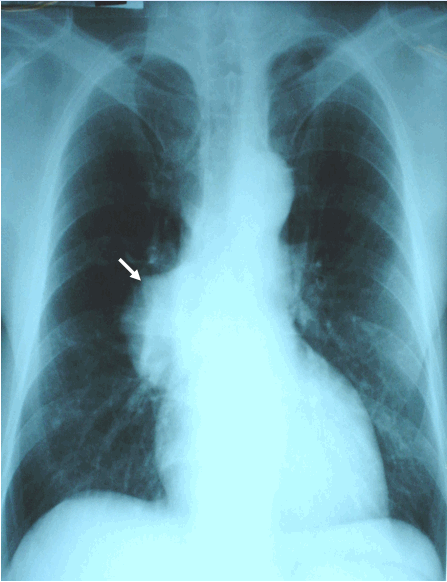

Hình ảnh K phổi phải thể ngoại vi ở phía sau trên chụp phổi thẳng ở bệnh nhân nam, 62 tuổi - Ung thư phổi phải